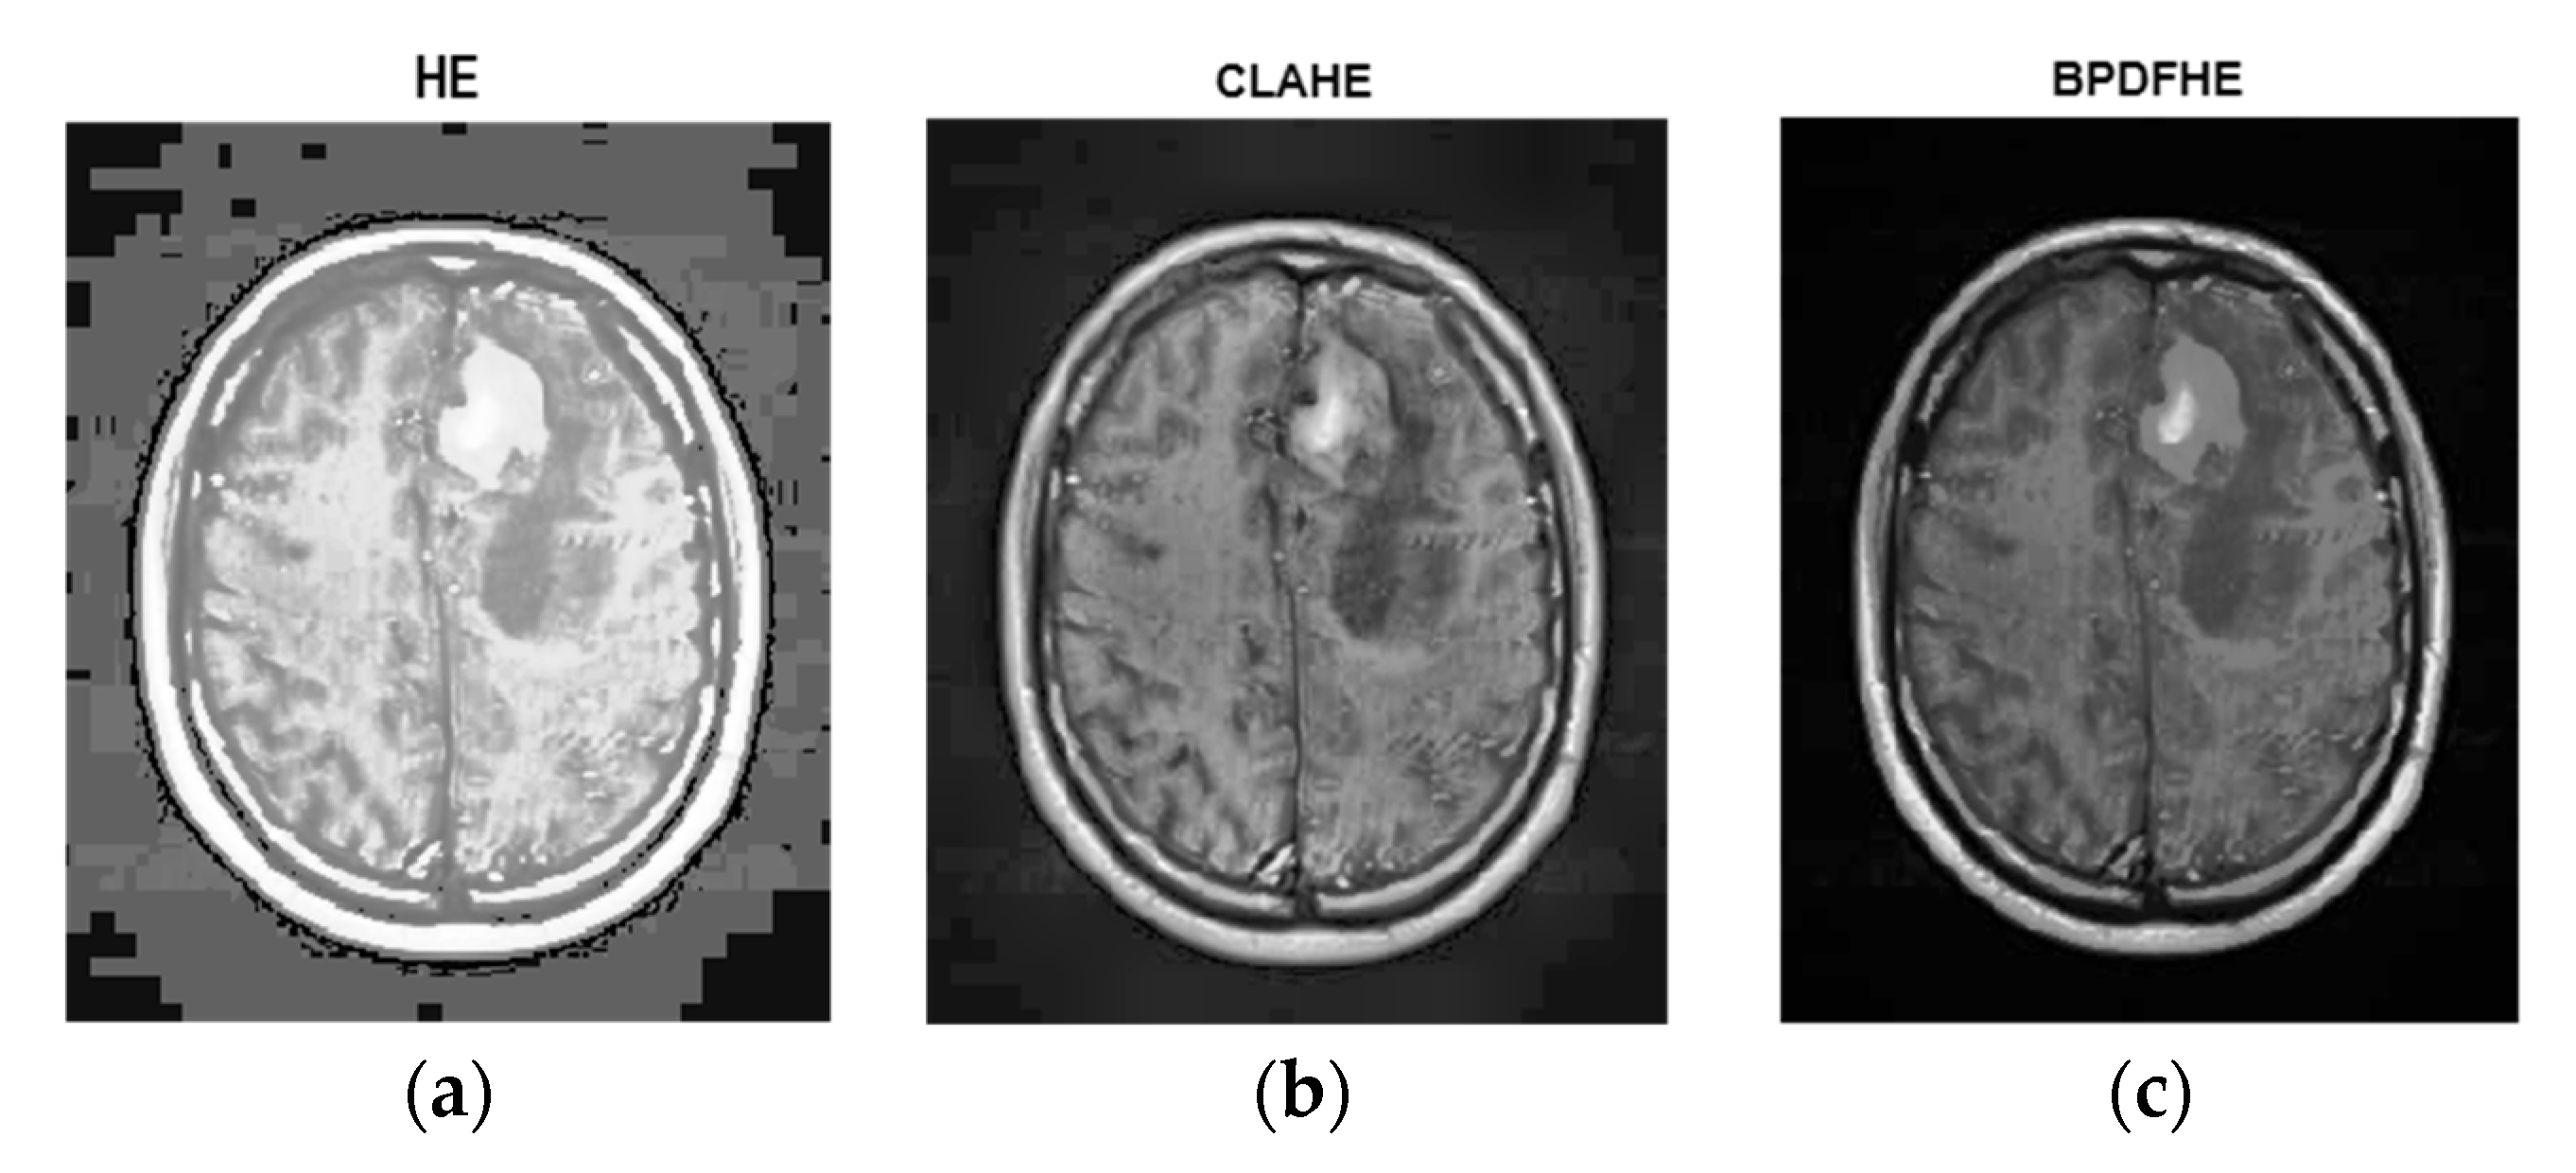

The following figures are the enhanced images with their corresponding histograms (HE, CLAHE, and BPDFHE) for the original images.

Figure 4a is the original. Figure 4b is its histogram representation. Figure 5a–c represents the same image enhanced via different preprocessing methods, i.e., HE, CLAHE, and BPDFHE, and Figure 6a–c is their respective histograms.

Figure 5.

Preprocessed with (a) HE, (b) CLAHE, and (c) BPDFHE.